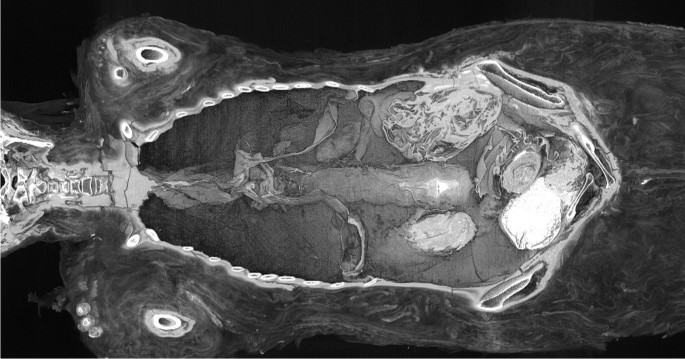

According to a new study in the Journal of Archaeological Science, X-rays and computer tests finally revealed the mummy’s true identity, showing the small hands and feet of a fetus. Researchers in Poland said it’s the first and only known case of a well-preserved mummified pregnant woman.

Researchers believe the woman was between 20 and 30 years old when she died. The size of the baby’s skull suggested she was about 26 to 28 weeks pregnant. The cause of death is not known.

X-rays and computer tests revealed the mummy’s true identity. Warsaw Mummy Project